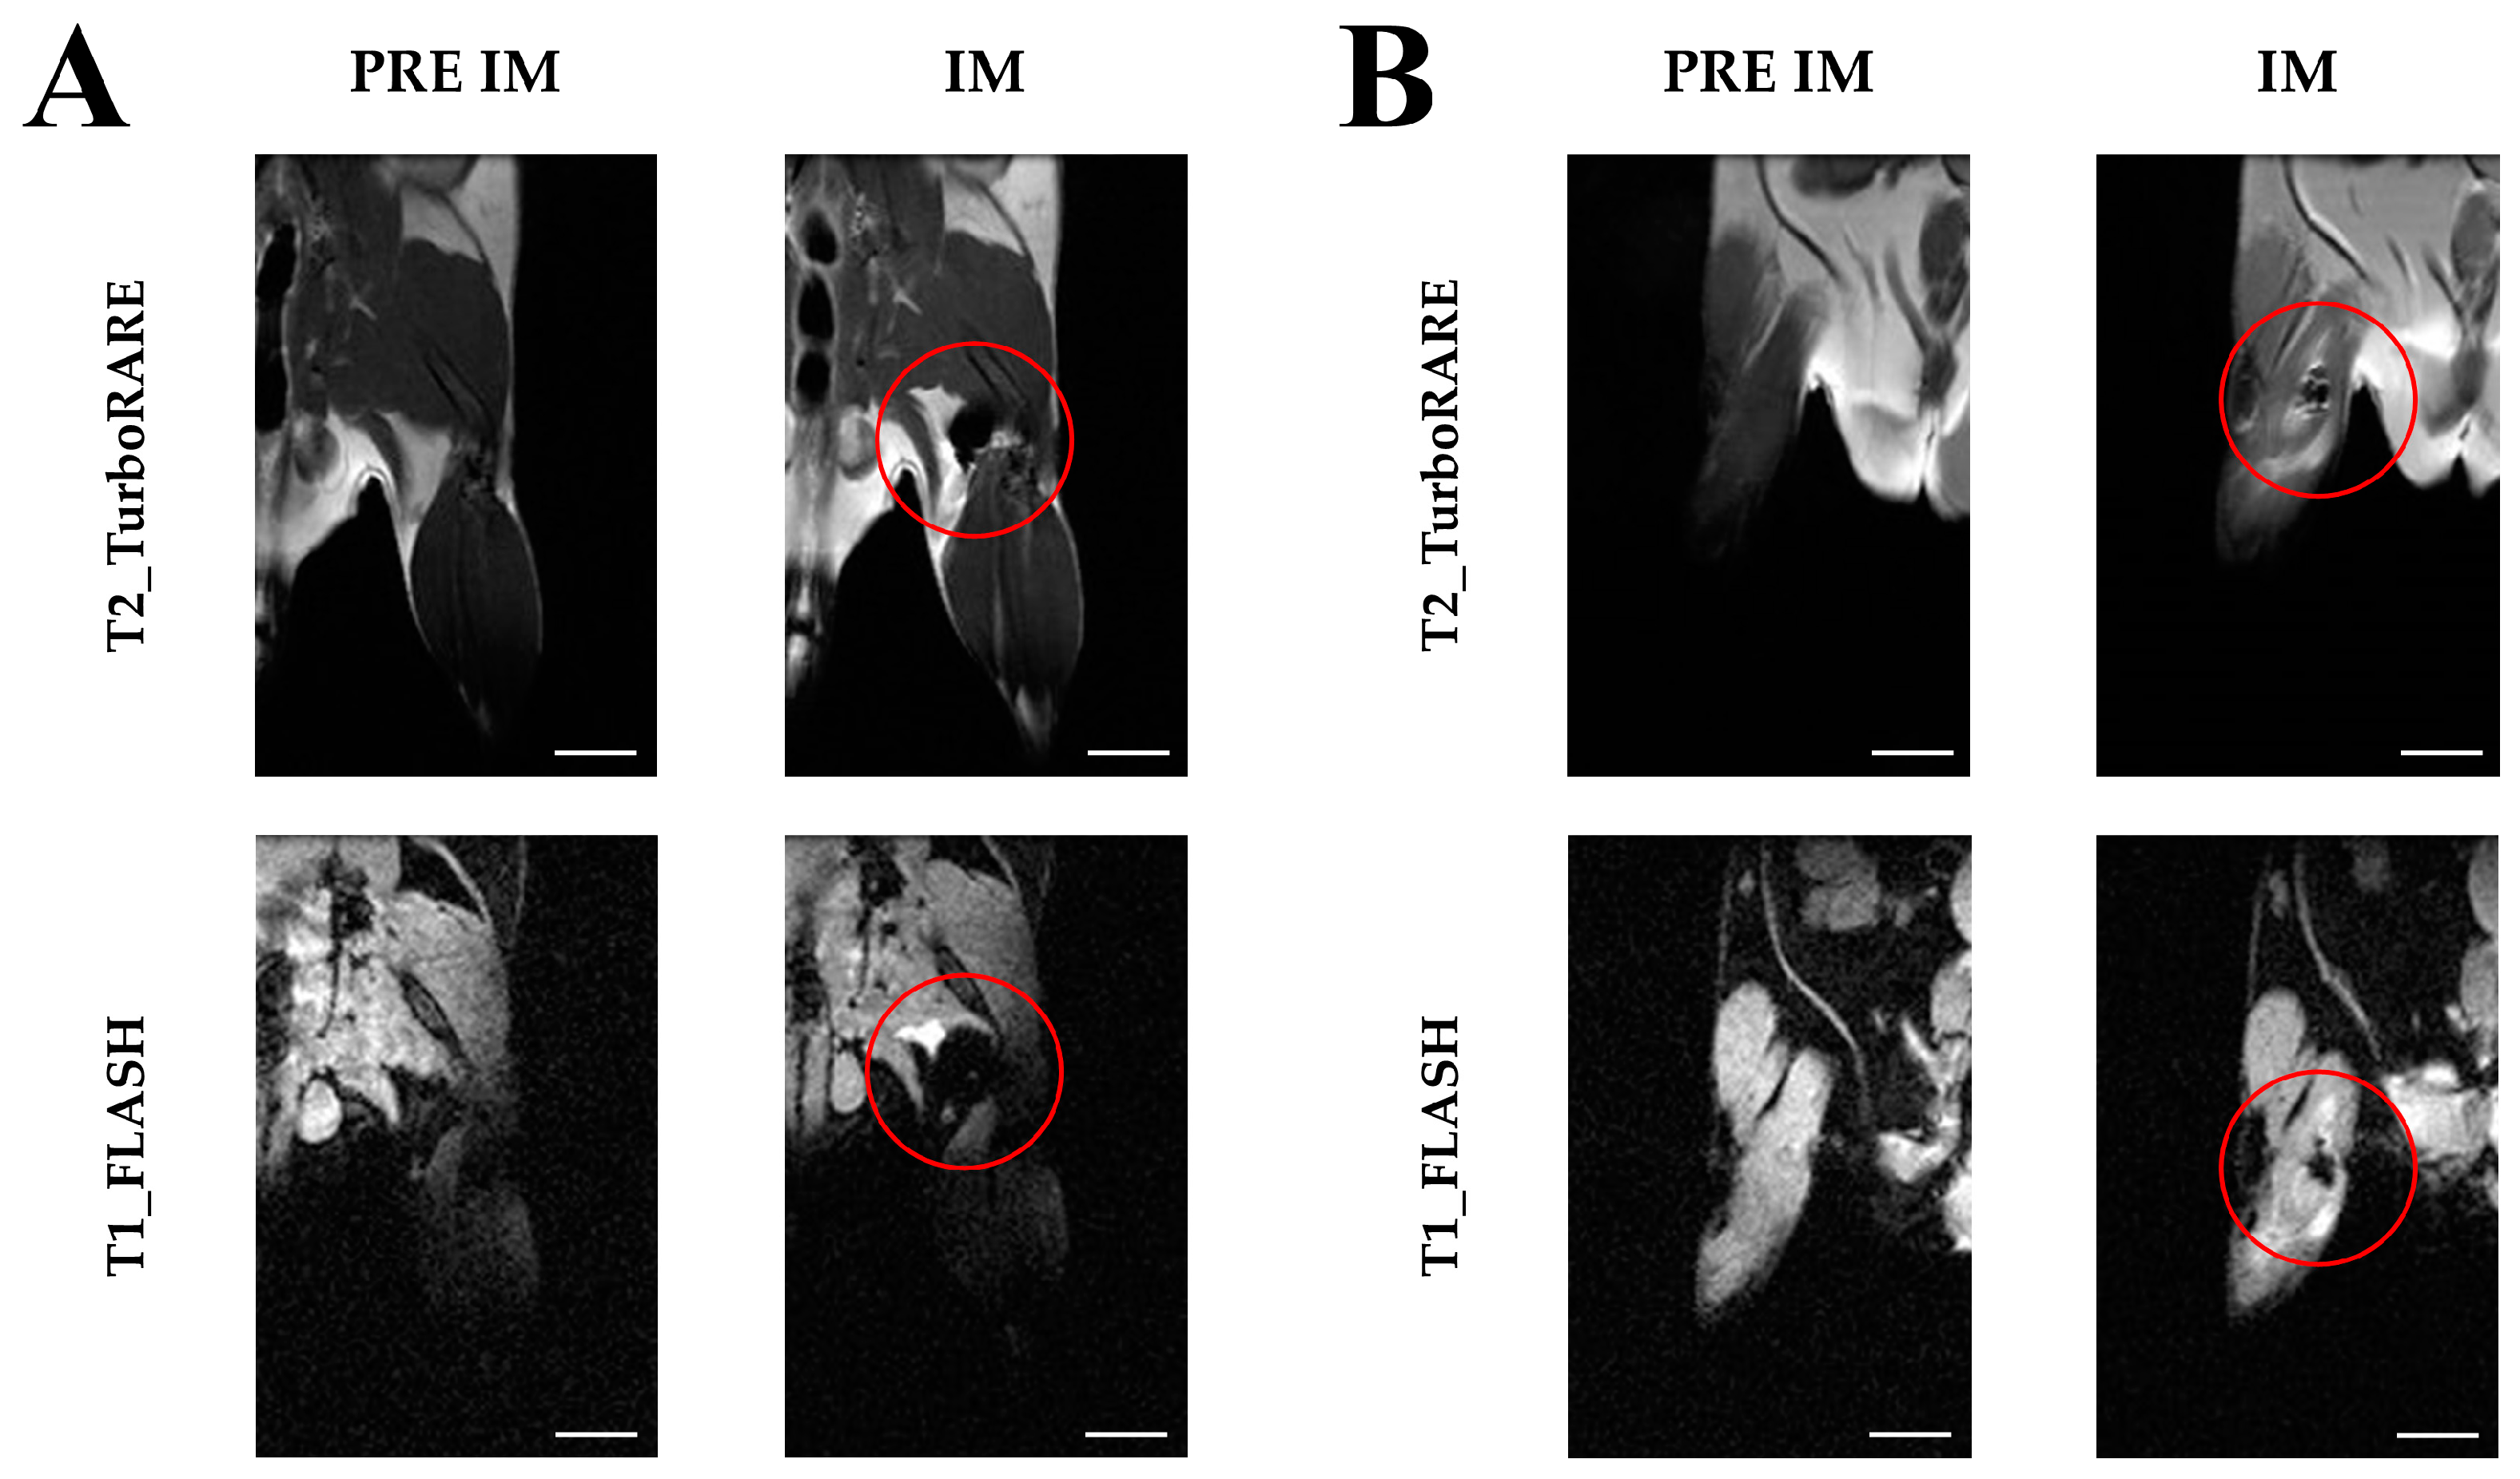

2.3. Imaging with Magnetic Resonance